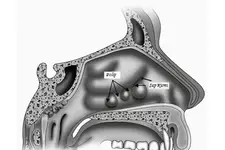

Ses telleri, sesin üretilmesinde kritik bir rol oynayan ve larenks içerisinde yer alan iki kaslı yapıdır. Bu yapılar, çeşitli etkenler sonucunda tahriş olabilir ve bu tahrişin sonucunda ses tellerinde polip oluşumu meydana gelebilir. Polipler, ses tellerinin yüzeyinde oluşan benign (iyi huylu) tümörlerdir ve genellikle ses kalitesini olumsuz yönde etkiler. Bu makalede ses tellerinde poliplerin belirtileri ve tedavi yöntemleri ayrıntılı bir şekilde ele alınacaktır. Ses Tellerinde Poliplerin Belirtileri Ses tellerinde polip oluşumunun belirtileri, hastalığın evresine ve poliplerin boyutuna göre değişkenlik gösterebilir. Genel olarak aşağıdaki semptomlar gözlemlenebilir:

Bu faktörler ses tellerinde tahrişe yol açarak poliplerin gelişiminde rol oynamaktadır. Tanı Süreci Ses tellerinde polip tanısı genellikle kulak burun boğaz uzmanı tarafından yapılır. Tanı süreci aşağıdaki adımlardan oluşabilir: